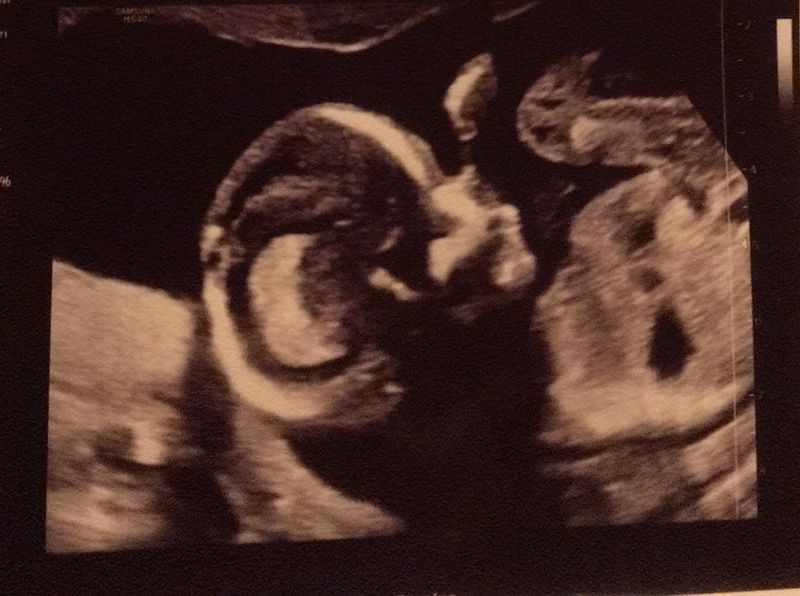

We zagen een wormpje op de echo

De eerste weken gingen voorbij. Ik had er vertrouwen in. Net als bij de vorige zwangerschappen had ik last van bloedverlies. Dat maakte me toch weer onzeker. Waar waren we aan toe? Gelukkig mochten we op vrijdag 25 september voor een vroege echo naar de verloskundige. Er werd met een inwendige echo gekeken. Bij mij was er op deze manier bijna niks te zien. De woorden van de verloskundige waren dan ook: “Dit ziet er voor nu niet goed uit”. Voor de zekerheid wilde ze toch nog even kijken met de uitwendige echo. En ja hoor, daar zat hij. Een klein wormpje met een kloppend hartje. Hij zat gewoon goed verstopt. Na deze echo vertelden we het onze twee kinderen. Wat waren ze verbaasd, maar ook ontzettend blij. “Ons kindje”, zeiden ze, “jij bent echt een kindje van ons alle vier”.

Dinsdagavond 8 december was de echo bij de verloskundige. Er werd naar het geslacht gekeken. Alles zag er goed uit. Blij en opgelucht. We kregen het geslacht in een enveloppe en de juiste kleur confettikanonnen mee.

De 20 weken echo

Het was woensdag 30 december. Deze ochtend stond de 20 weken echo gepland. Zelf heb ik een afwijking aan de urineleiders en dat is reden om een GUO te krijgen in het ziekenhuis. Ik was hier 19.5 weken zwanger en al deze weken klonk er een stemmetje in mijn hoofd die zei: “Wees nog niet te blij Maartje. Koop nog maar niks. Eerst de 20 weken echo afwachten, dan kijken we wel verder. Eerst zien, dan geloven”. De gynaecoloog die de echo uitvoerde was dezelfde als bij Jake bijna 8 jaar geleden. Dat was fijn, een bekend gezicht. Ik mocht gelijk gaan liggen. Phoe, wat was ik zenuwachtig. Ze praatte gelukkig veel over wat ze zag en ze was heel enthousiast. Een knap kind vond ze hem. Hij was heerlijk aan het spartelen en trapte zo af en toe tegen de doppler aan. Doordat hij zo druk was, was het lastig kijken naar zijn hartje. Ze besloot eerst alvast even de gegevens in de computer te zetten over alle goede dingen die ze had gezien. Wij zochten er nog niks achter en waren blij dat alles er goed uit zag. Achteraf denk ik dat ze misschien tijd aan het rekken was om te bedenken wat ze wellicht al vaag had gezien. Ze ging verder kijken naar het hartje. Voor een leek zag het er prima uit. Twee kamers, twee boezems. De bloeddoorstroming werd gecontroleerd. De gynaecoloog bleef maar kijken en kijken. Dat leek wel eeuwen te duren.